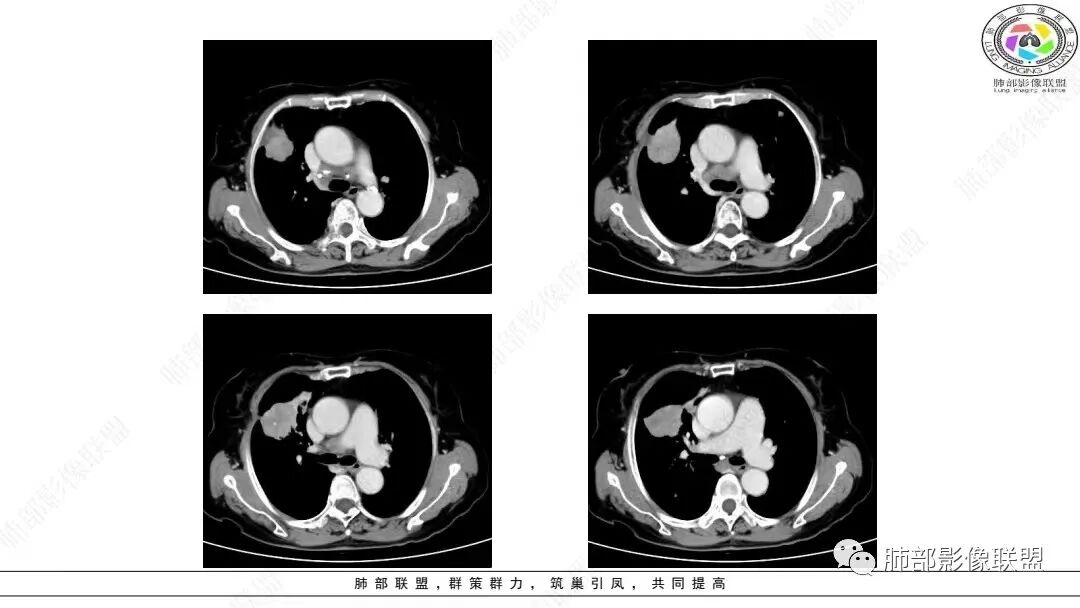

2.影像学特点:右肺上叶前段胸膜下不规则较大团块影,边界清楚欠光整,浅分叶,肺血管支气管出入,边缘膨隆胸膜凹陷具有一定张力,未见典型粗短毛刺,部分围以边界清楚的磨玻璃影,灶周小叶间隔增厚。块影密度不均,渐进性强化,可见砂砾样钙化,未见明显液化坏死或空洞。增强后病灶显示渐进性强化。MIP显示病灶内肺动脉穿行、并部分肺动脉受侵变细。纵隔及右锁骨上(胸廓入口)见肿大淋巴结。两肺可见多发大小不一的结节影,边界清楚,随机分布。

病灶较大较光整,支气管出入,缀以边界清楚磨玻璃影,有一定张力,不均匀强化,疑及肺腺癌或者大细胞肺癌都在情理之中。双肺多发病灶,符合转移瘤特征。     注意胸椎体溶骨性吸收破坏,突破骨皮质,经验上这样的改变更支持转移而不支持淋巴类肿瘤。

目前部分研究提示肺LELC大多以单发周围型肿块为主,多发生肺下叶,多数病灶可见分叶及毛刺征。Ma等口1发现,41例肺LELC患者中30例(73.17%)表现为较大的中央型肿块,以右肺中叶和左肺下叶多见,边界清楚,呈分叶状,常引起阻塞性肺炎。本组肺LELC中央型占54.10%,多发生于右肺中叶、两肺下叶,最大径平均(5.42±2.64)ClTI,肿块型多见(79.92%),边界较清,边缘常见分叶,且以浅分叶为主,可伴毛刺,超过半数(54.10%)伴有阻塞性肺炎或肺不张改变。

本组大部分病灶(64.75%)CT平扫密度均匀;增强后多数病灶以中度(71.75%)、渐进性强化(75.13%)为主,动脉期病灶内常见异常细小杂乱血管影(55.96%)。    笔者据此认为密度均匀且不易出现坏死、呈中度渐进性延时强化为肺LELC的特点,可能与病灶内部含有丰富的淋巴细胞浸润和大量纤维组织增生及胶质有关;病灶内部分细小杂乱血管影可追踪为支气管动脉,推测可能为新生肿瘤血管,提示肿瘤血供丰富,不易出现坏死;但新生肿瘤血管通常不成熟,血管通透性增高,致使对比剂外渗,使肿瘤表现为延迟强化。肺LELC生长较快时,由于血供不足,也可出现液化坏死及钙化等改变。肺LELC密度均匀、液化坏死较少及延迟强化,可作为其与肺鳞癌或腺癌的鉴别要点。

多数学者认为血管支气管包埋征是肺LELC的特征性表现。本组41.97 0A(81/193)病灶内部动脉期见血管包埋征,而血管形态正常,无明显受侵、狭窄,与上述研究报道相符,可能提示肺LELC具有类似淋巴瘤相似的特点,即易浸润周围结构,引起间质增厚、肺泡壁破坏及肺泡腔充盈,但较少侵犯血管[1 3|。但本组108例(108/193,55.96%)表现为血管受侵、狭窄,75.82%支气管受累狭窄闭塞,可能提示肺LELC病灶内血管受侵狭窄及支气管破坏较淋巴瘤更多见[1 3|,较大肺LELC病灶更易出现血管、支气管受侵、破坏。